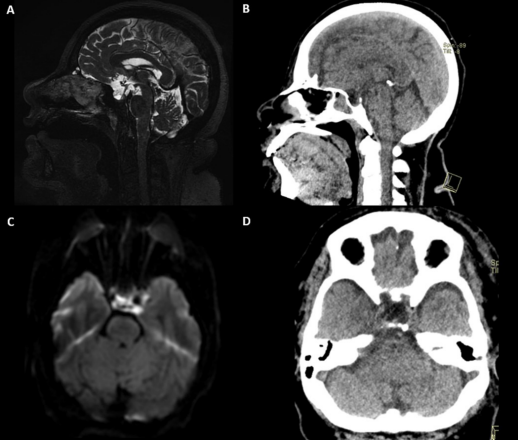

56-year-old female with clinical history of systemic arterial hypertension, carbohydrate intolerance, and dyslipidemia with current management of her comorbidities; no hormonal symptoms or laboratory abnormalities were reported. The patient showed at the Neurosurgery department reporting visual disturbances of her right eye and intermittent oppressive headache in frontal region, being previously assessed by the ophthalmology service and diagnosed with right temporal hemianopsia; however, the imaging study showed a multilobulated cystic lesion in the suprasellar and retrosellar region that invaded the left optochiasmatic cistern with ipsilateral extension that caused retraction of the pituitary stalk. MRI showed restricted diffusion on DWI and increased signal intensity on T2 sequence (Figure 1). For this reason, we decided to perform a left transciliary supraorbital approach; making a 4 cm incision and a craniotomy approximately 30 mm wide x 20 mm high, observing a pearly, soft, and avascular lesion, mostly invading the left optochiasmatic cistern that involved neurovascular structures (left carotid artery, optic nerve left and optic chiasm) (Figure 2). A complete resection of the lesion was performed, without complications, allowing us to discharge the patient in the first 72 hours. The histopathological report showed a keratinized stratified squamous epithelium confirming the diagnosis of an epidermoid tumor (Figure 3).

Figure 1 Preoperative MRI compared with postoperative CT. A. MRI. T2-weighted sagittal view with hyperintense lesion with suprasellar, parasellar and retrosellar extension of left predominance that displaces the pituitary stalk and involves blood vessels. B & D. Hypodense image confined to the sellar region and postsurgical changes that demonstrate absence of occupational lesion with modification of the anatomy towards normality. C. DWI sequence shows a hyperintense lesion with respect to the brain parenchyma, causing diffusion restriction.